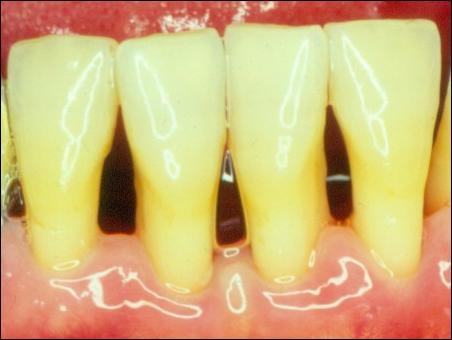

牙結石是如何附著在牙齦周圍的

掛滿了結石的牙齦組織紅腫